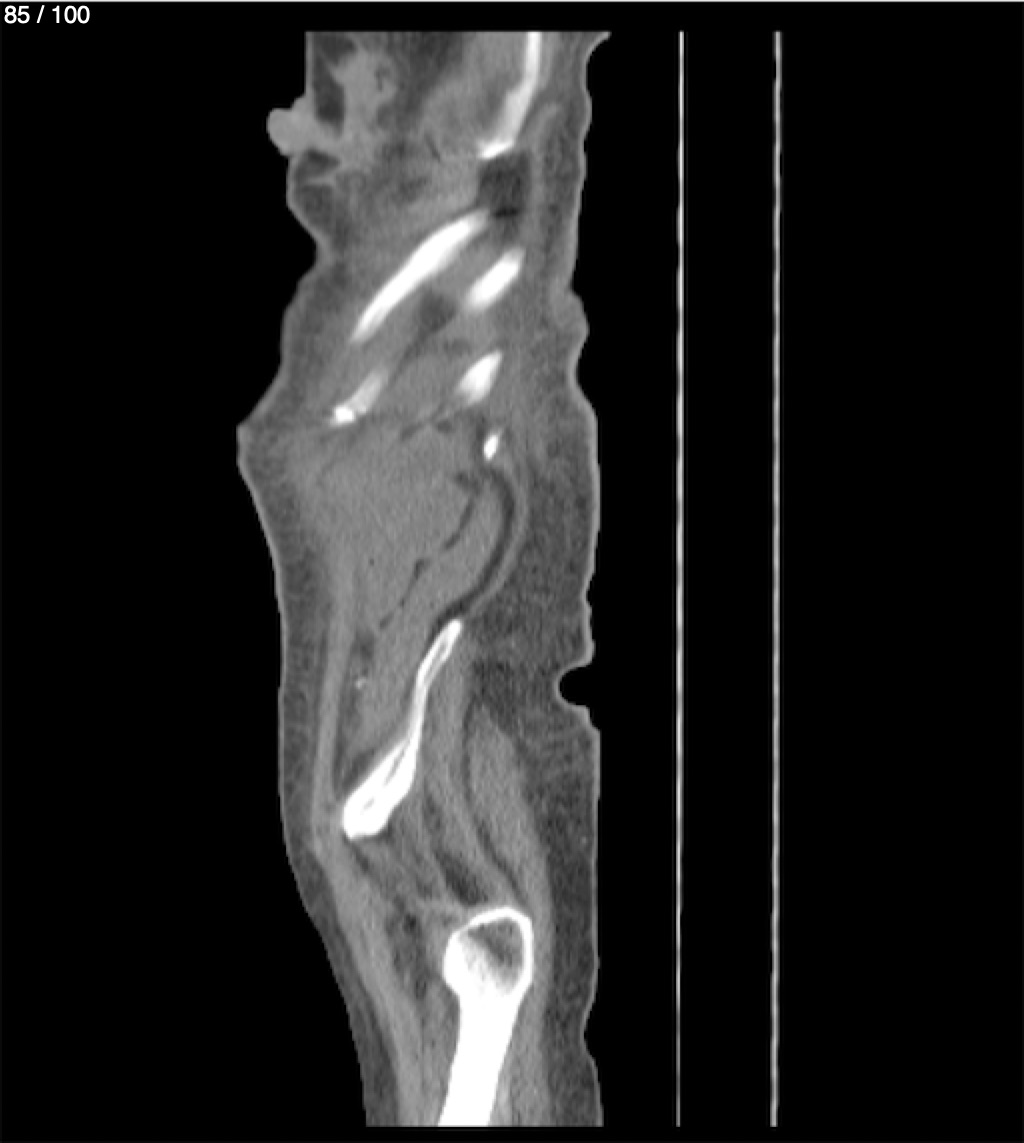

Hilda Geronimo Mendez 60A - T.C Abdomen Simple